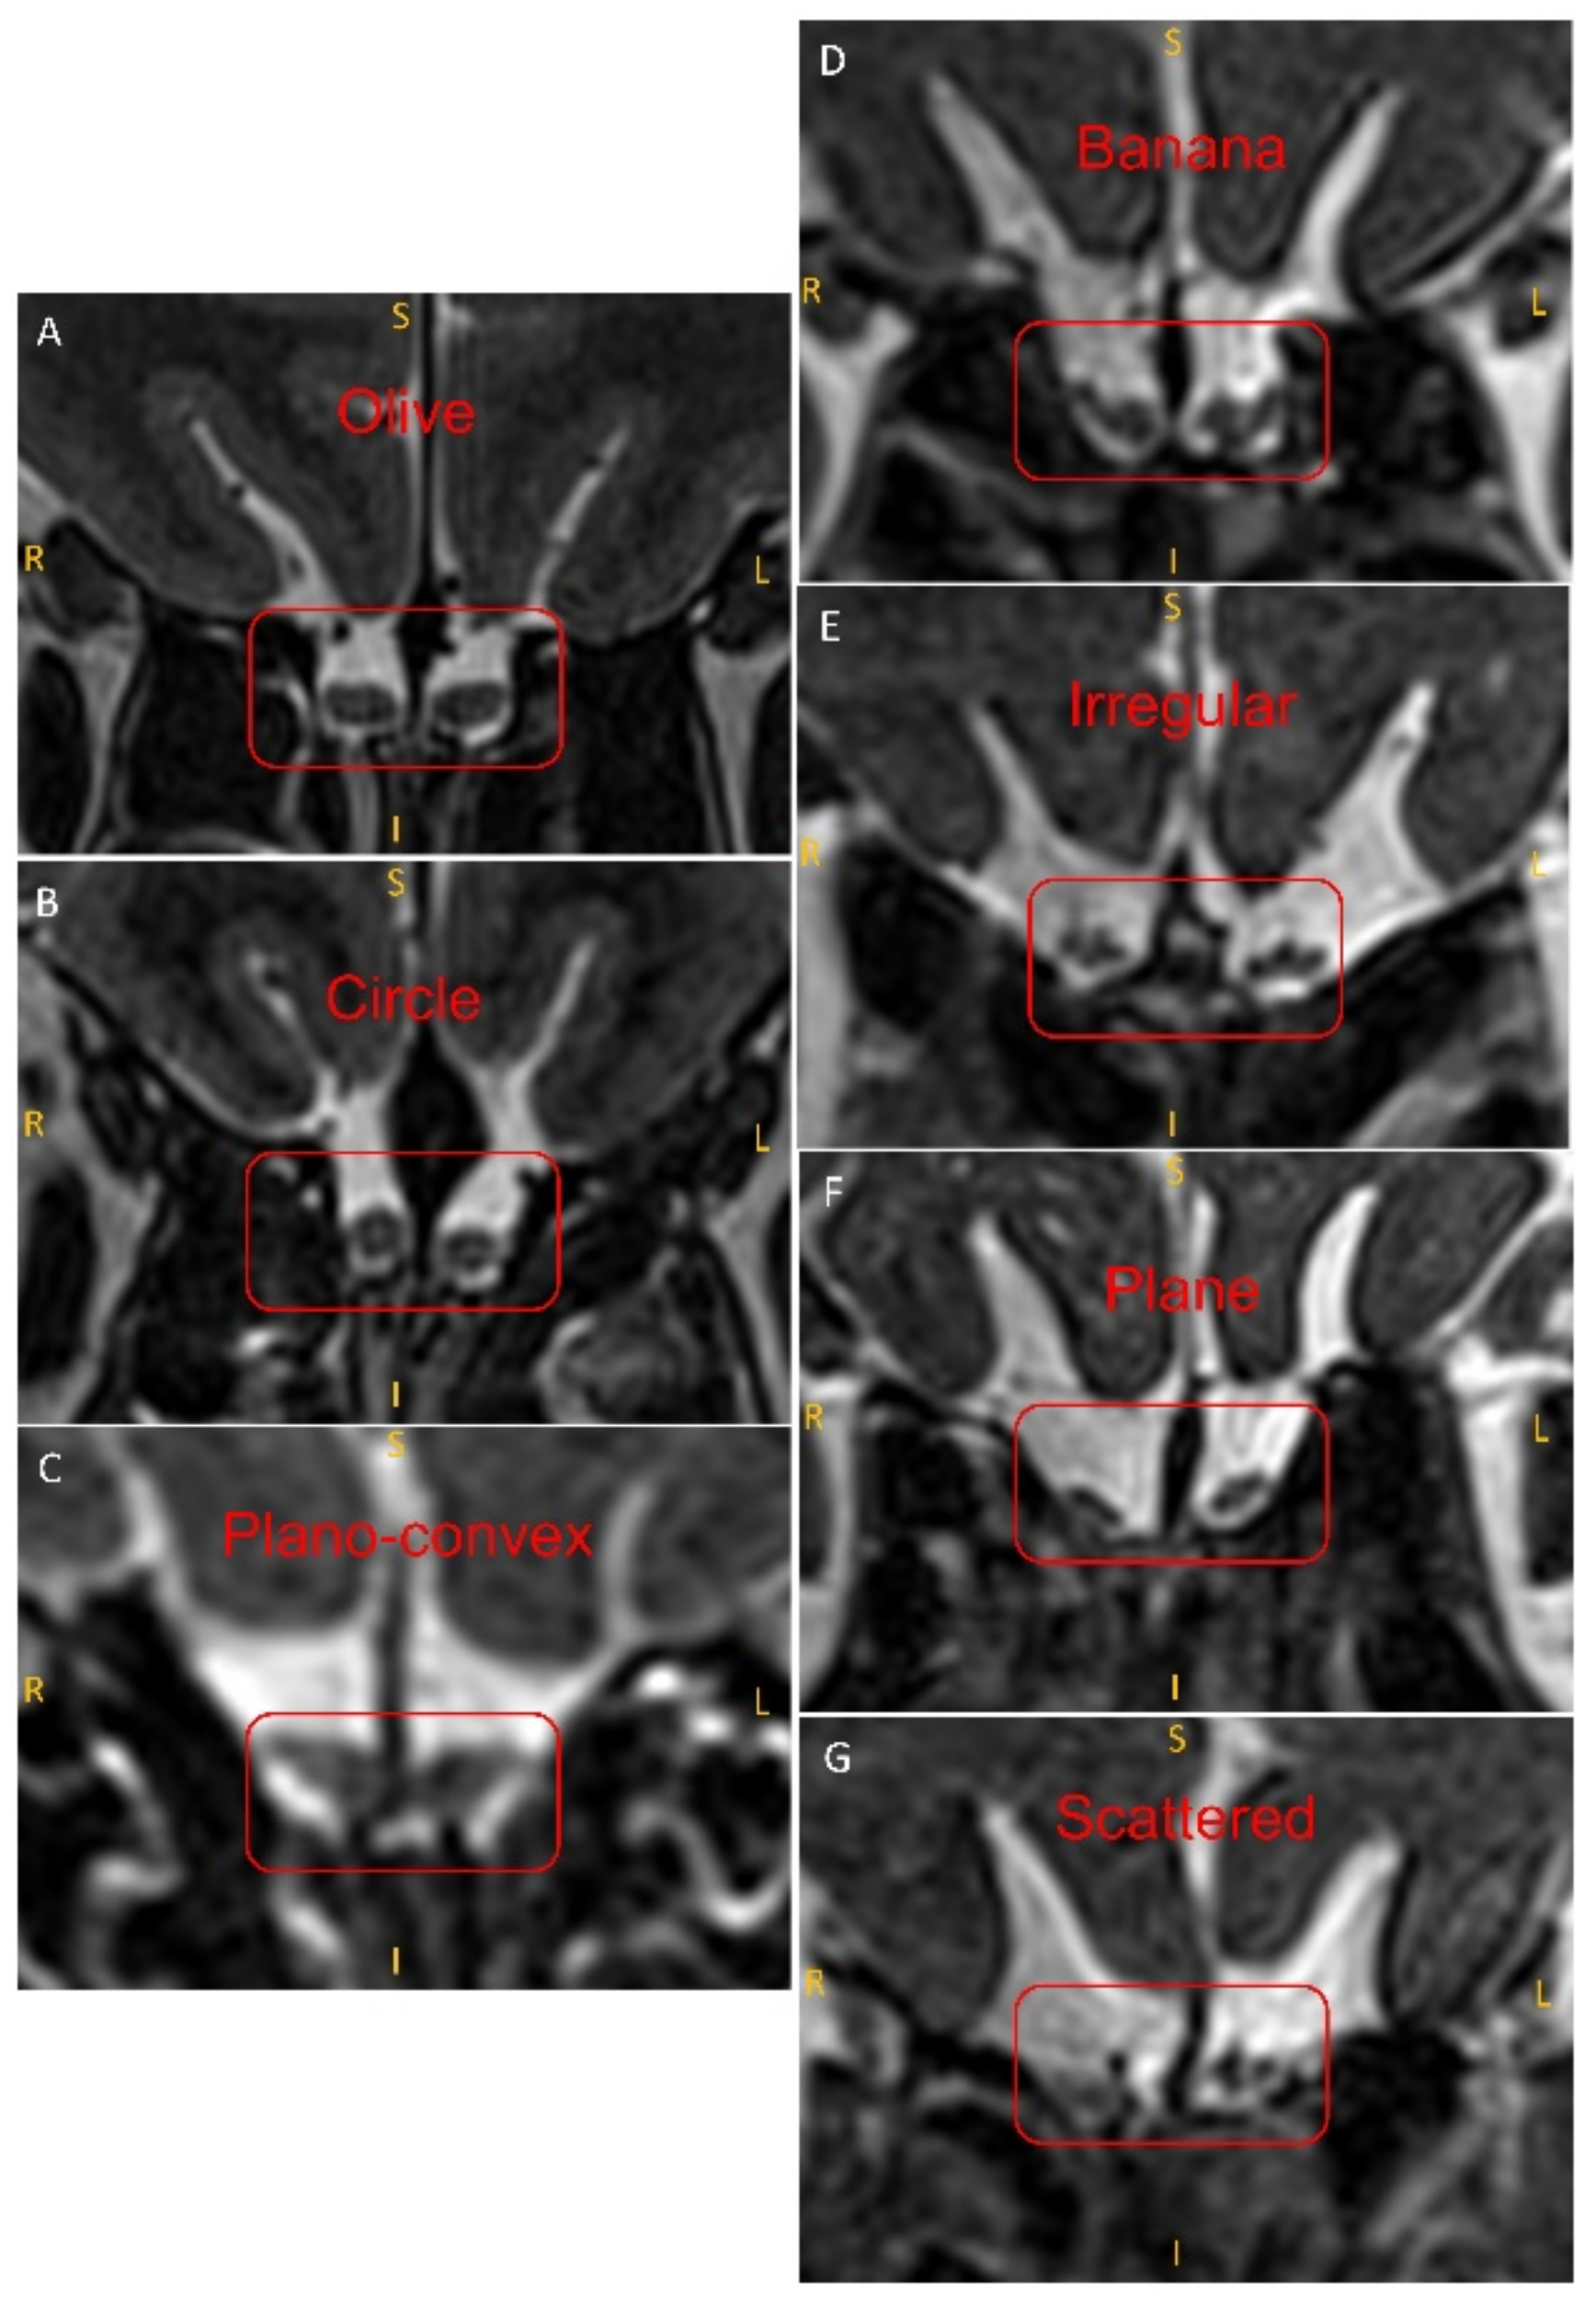

2.4. Evaluation of the Shape of the OB

| Causes, OB Shape | Olive, no. (%) | Circle, no. (%) | Plano-Convex, no. (%) | Banana, no. (%) | Irregular, no. (%) | Plane, no. (%) | Scattered, no. (%) | Total |

|---|---|---|---|---|---|---|---|---|

| Sinonasal | 4 (19.0%) | 3 (14.3%) | 2 (9.5%) | 6 (28.6%) | 3 (14.3%) | 1 (4.8%) | 2 (4.8%) | 21 |

| idiopathic | 6 (10.5%) | 5 (8.8%) | 1 (1.8%) | 18 (31.6%) | 9 (15.8%) | 4 (7.0%) | 14 (24.6%) | 57 |

| Parkinson’s disease | 1 (9.1%) | 4 (36.4%) | 0 (0.0%) | 3 (27.3%) | 3 (27.3%) | 0 (0.0%) | 0 (0.0%) | 11 |

| PIOD | 3 (5.2%) | 9 (15.5%) | 7 (12.1%) | 15 (25.9%) | 9 (15.5%) | 11 (19.0%) | 7 (12.1%) | 58 |

| PTOD | 9 (20.0%) | 0 (0.0%) | 4 (8.9%) | 11 (24.4%) | 12 (26.7%) | 3 (6.7%) | 4 (8.9%) | 45 |

| Total, no. | 53 | 36 | 23 | 21 | 19 | 26 | 14 | 192 |